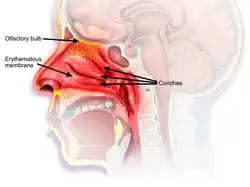

The characteristic presentation of RM involves nasal congestion without rhinorrhea, postnasal drip, or sneezing following several days of decongestant use.[2] This condition typically occurs after 5–7 days of use of topical decongestants. Patients often try increasing both the dose and the frequency of nasal sprays upon the onset of RM, worsening the condition. The swelling of the nasal passages caused by rebound congestion may eventually result in permanent turbinate hypertrophy, which may block nasal breathing until surgically removed.[3]